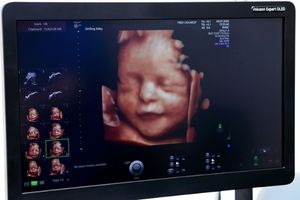

تشخیص بارداری: سونوگرافی یکی از روشهای استاندارد برای تأیید بارداری است. در این روش میتوان سن بارداری، تعداد جنینها، موقعیت جنین و وجود یا عدم وجود مشکلاتی مانند حاملگی خارج از رحم را بررسی کرد.

بررسی رشد و سلامت جنین: سونوگرافی در طول بارداری برای بررسی وضعیت رشد جنین، سلامت قلبی-عروقی آن و بررسی مشکلات احتمالی مانند نقصهای مادرزادی استفاده میشود.